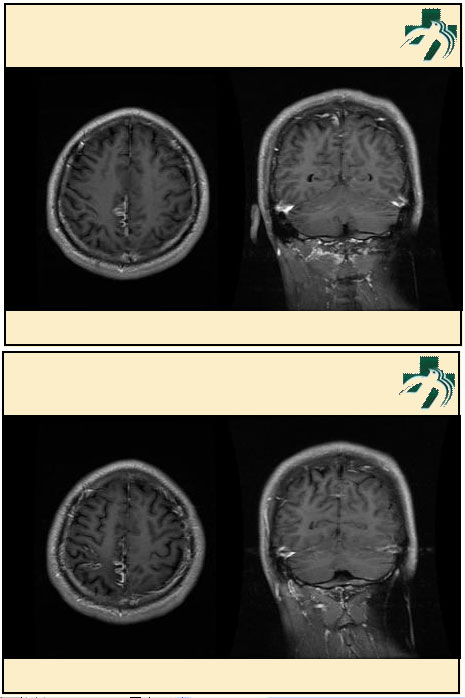

奴卡氏菌感染

第九期三博

读片会

病例之四

北京协和医院 提供

男性,22岁。自觉虫咬后皮疹、肢体麻木4月